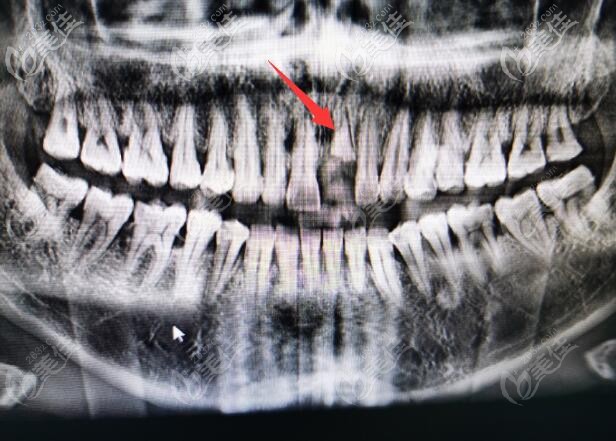

前门牙种植好后拍的CT照片▼

在复诊的时候,我还专门问了他,是不是前牙种植成功率低?

李医生说,前牙和后牙种植比较大的区别就是,前牙要考虑到美学因素,在美学基础上设计骨组织。

很多医生在给顾客种植的时候,只考虑顾客的牙槽骨,等一期手术结束,才发现出问题了。种植牙到是愈合的挺好,不过美观度欠佳。